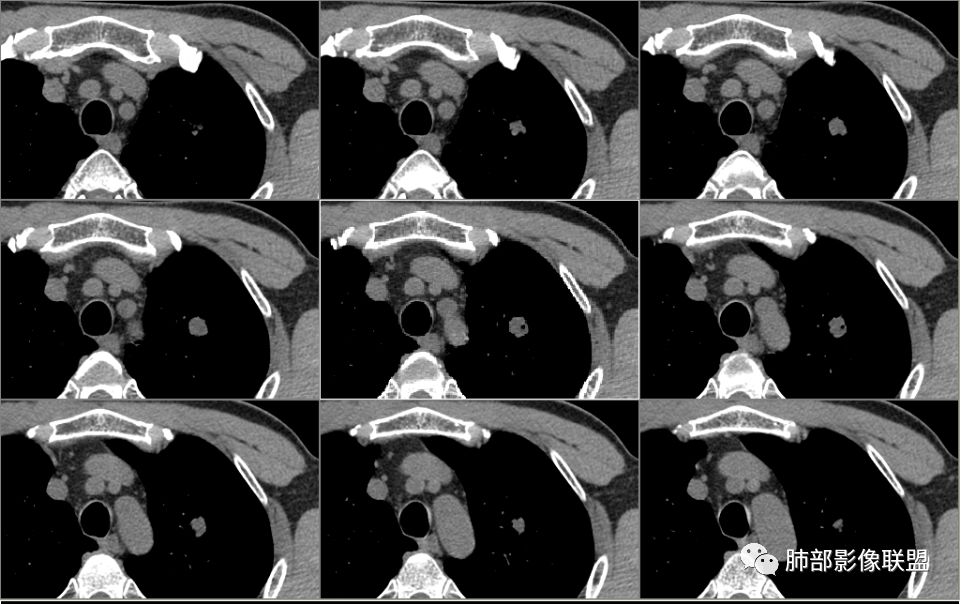

病例2肉瘤样癌的病理意见有些出乎预料,也充分说明病变及影像表现的复杂性。病灶小结节支气管截断、空泡、分叶、短毛刺、血管集束征等似乎均符合肺癌的影像特性。肺鳞癌及肉瘤样癌往往范围较小就可以出现坏死,但如果结节太小则很少能够在影像上观察到坏死区或空洞,没有增强扫描图像更是如此。